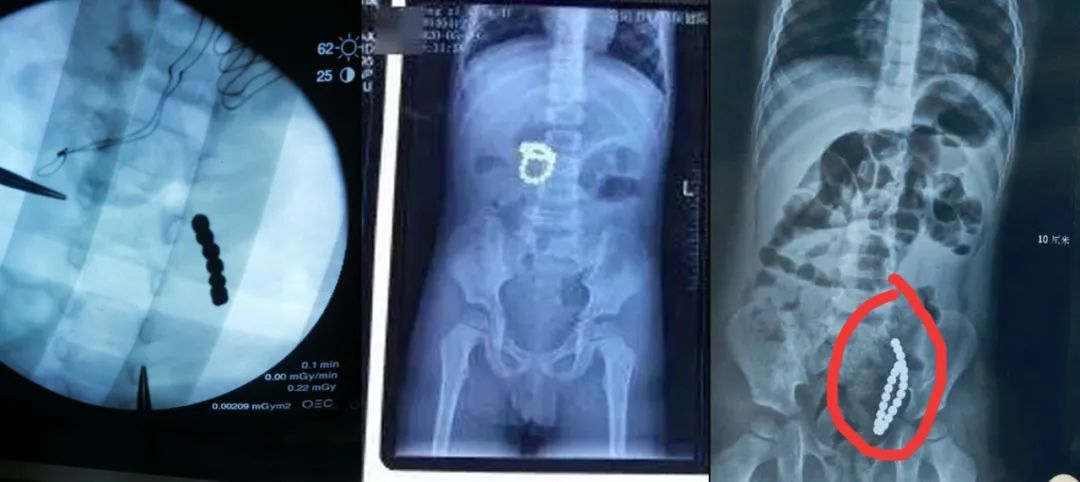

端午节那天,在网上看到一条新闻:成都三岁孩子误食22颗磁力珠,腹痛三天造成8处肠穿孔,情况十分危急。幸好及时做了手术,才转危为安。

当吞到一定数量的时候,磁力珠会因为磁力在体内连接在一起,容易造成肠穿孔或肠梗阻,严重的甚至会危及生命。